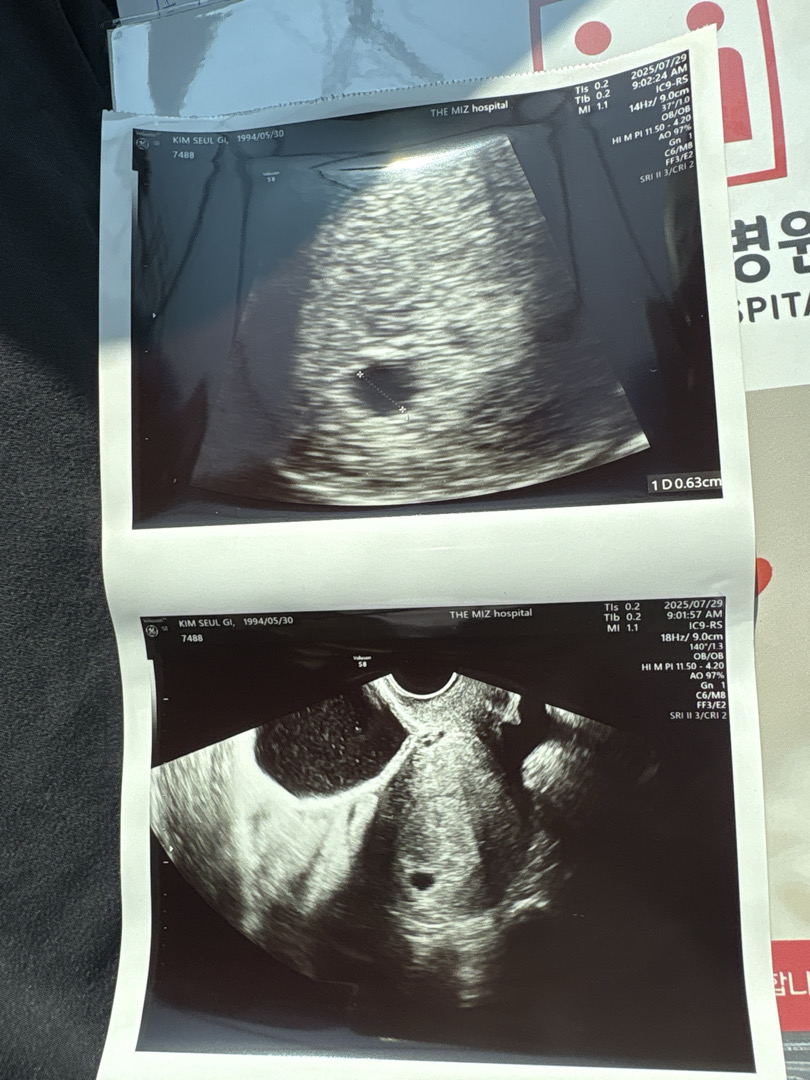

아기집 속도가 너무 더디다고 유산확률이 있다는데ㅠㅠ

일단 생리 불규칙이라 마지막 생리 시작일이 5월 20일 이었고 저번주에 아기집 처음 확인했어요! 오늘이 두번째로 초음파 보러갔는데 사진은 오늘 찍은 포음파 사진이고요 ㅠㅠ 예상 주수는 5주 6일차인데 지난주 21일에 피검사 수치 4380 그다음날은 5000몇이었어서 하루사이에 피검사수치가 믾이오르지않았고 ㅍ수치에 비해 저번주 아기집이 너무 작다하셨어요 ㅠㅠ 8뤌 5일에 ㅇ심장소리 확인하고 안들리면 유산확률이 너무높다는데.. ㅠㅠㅠㅠ 무섭다